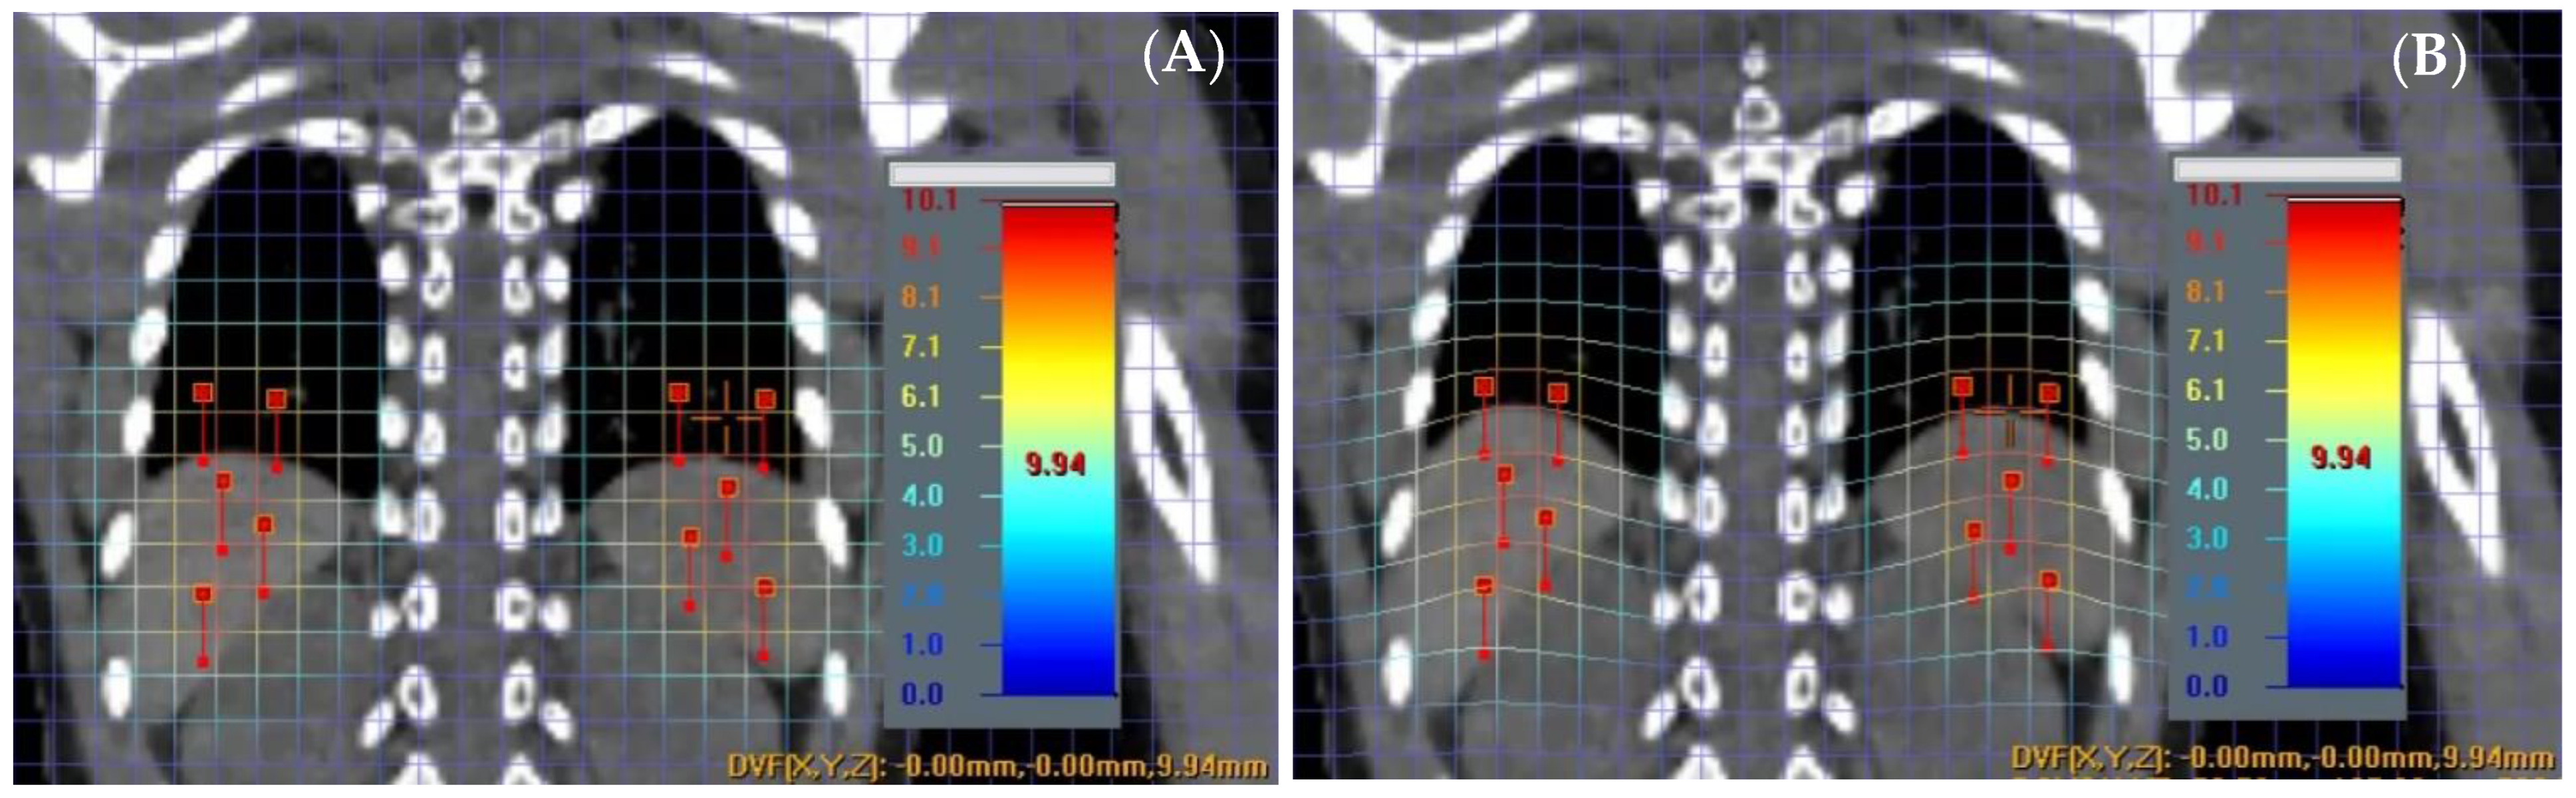

A virtual phantom was created using a patient’s CT images to mimic splenic motions at various displacements of ±3 mm, ±6 mm, ±8 mm, and ±10 mm in the inferior to superior direction. To achieve this, a specialized image manipulation software called ImSimQA (version 4.3.2.) (Oncology Systems Limited, Shropshire, UK) was employed. The software created deformation vector fields, which were then applied to produce artificial CT images with precisely known deformations of ±0.1 mm uncertainty. Figure 1 illustrates a patient case with simulated splenic motion with an associated magnitude of 10 mm ± 0.1 mm in the superior direction, depicted by overlaid deformation vector fields on CT images before Figure 1A and after Figure 1B manipulation. To achieve this deformation, a set of 10 anchor points was strategically placed to deform the upper abdomen region, including the diaphragm, spleen, and liver, by known amounts.

Figure 1. A deformed image of before (A) and after (B) is shown with 10 anchor points. Cross hair reads a net deformation of 9.94 mm for the spleen in superior direction.